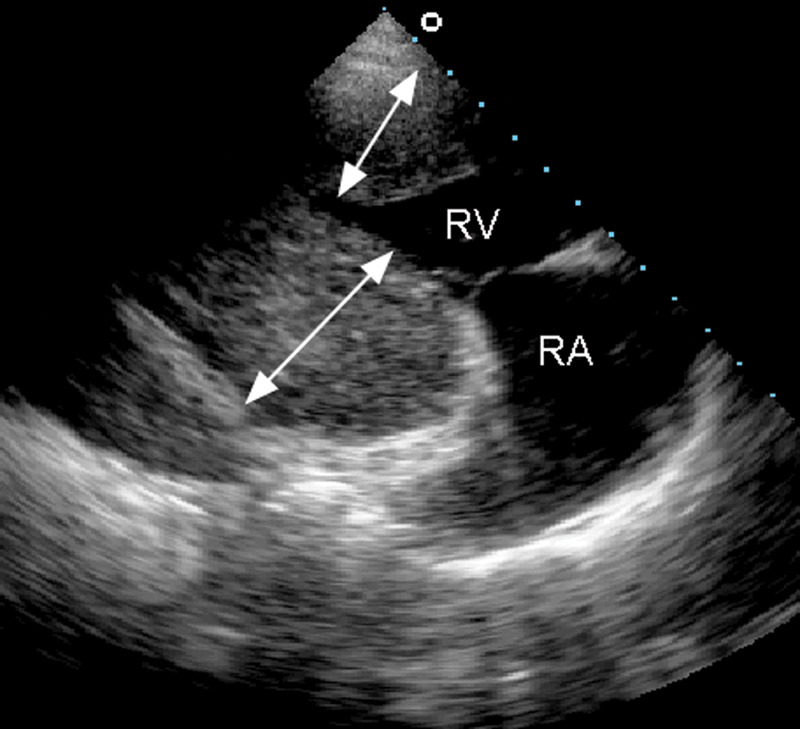

فحوصات تشخيصية لبعض امراض القلب والشرايين التاجية